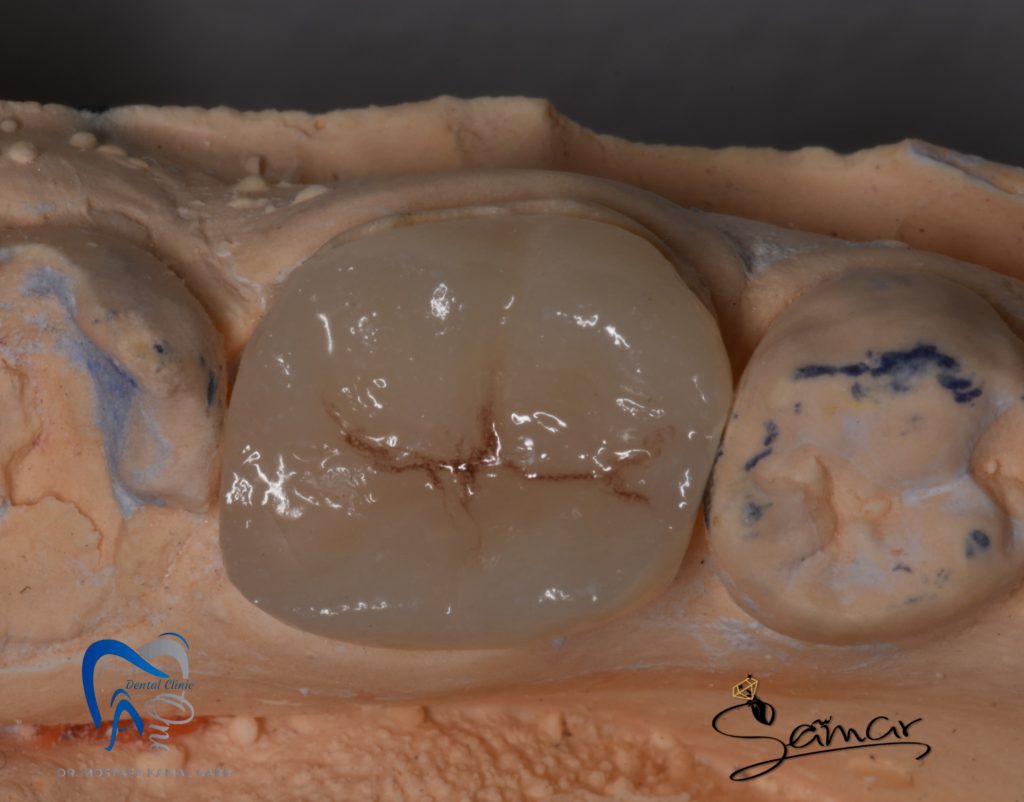

Final design

Bonding using heated composite